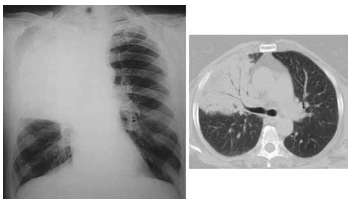

Paciente do sexo masculino, 42 anos, tabagista, etilista de 1 litro de destilado por dia, procura atendimento médico com queixa de tosse com expectoração esverdeada há cerca de 6 dias. Associado ao quadro relata inapetência, febre de até 40 graus concomitante a calafrios e tremores. Encontra-se, ao exame físico, desidratado, taquipneico leve, PA 120x70 mmHg, FC 102 bpm, temperatura = 38 ºC e saturação de O2 = 90%. Realizadas radiografia de tórax e tomografia computadorizada de tórax que estão ilustradas a seguir.

O agente etiológico mais provável envolvido no diagnóstico desse paciente é o(a)